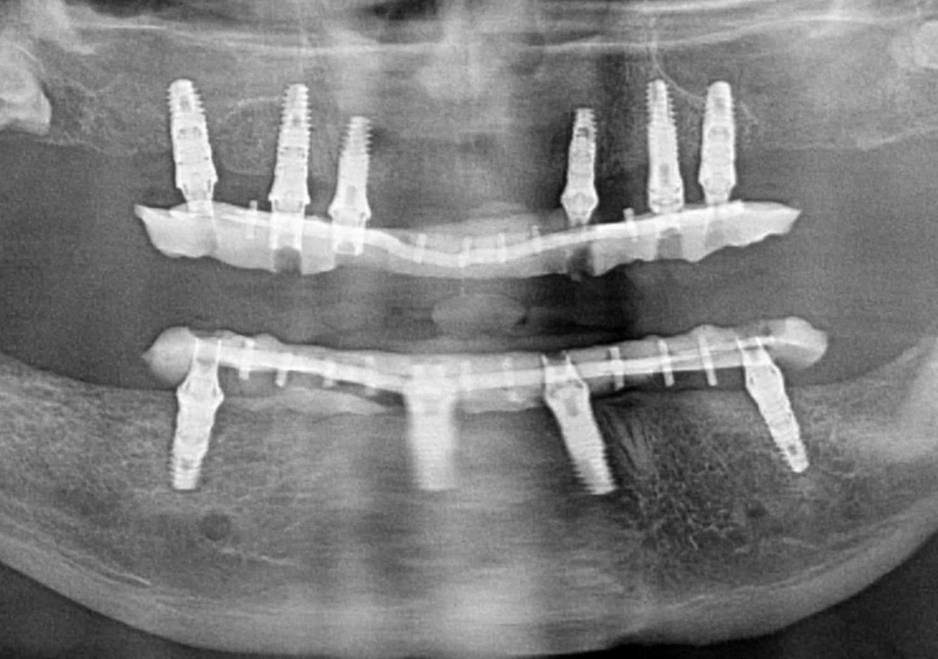

Each clinical case is individual, but there is a general pattern, as shown in the image below. Here, six implants were placed in the maxilla and four in the mandible.

An example of restoration of both dental arches: the dentures are reinforced, the maxilla has 6 implants for better load distribution in the loose bone, the mandible has 4 implants, which is sufficient, since the mandible bone is denser. YouTube/ Dr. Sergey Rozhnov /sergiodontologist

Such decisions are based on the fact that the bone tissue of the maxilla is not as dense as that of the mandible. Often, even in the anterior region, the density is D3, while in the posterior region, it is D4. However, proper selection of implant length, thread aggressiveness, and angled placement of distal implants allows for the creation of a stable structure even with four implants. We will discuss the selection of the number of implant lengths and diameters in more detail in the next part of this series.